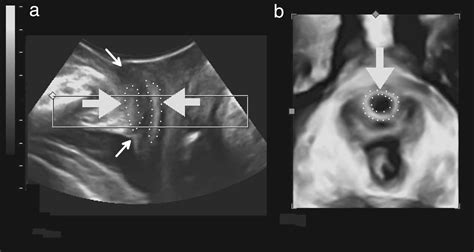

Diagnosing a Urinary Bladder Diverticulum requires imaging to visualize the bladder structure. Urologists typically utilize a combination of the following methods:

Ultrasound Non-invasive method to visualize the presence and size of the diverticulum.

Cystoscopy A camera is inserted into the bladder to inspect the bladder lining and the neck of the diverticulum.